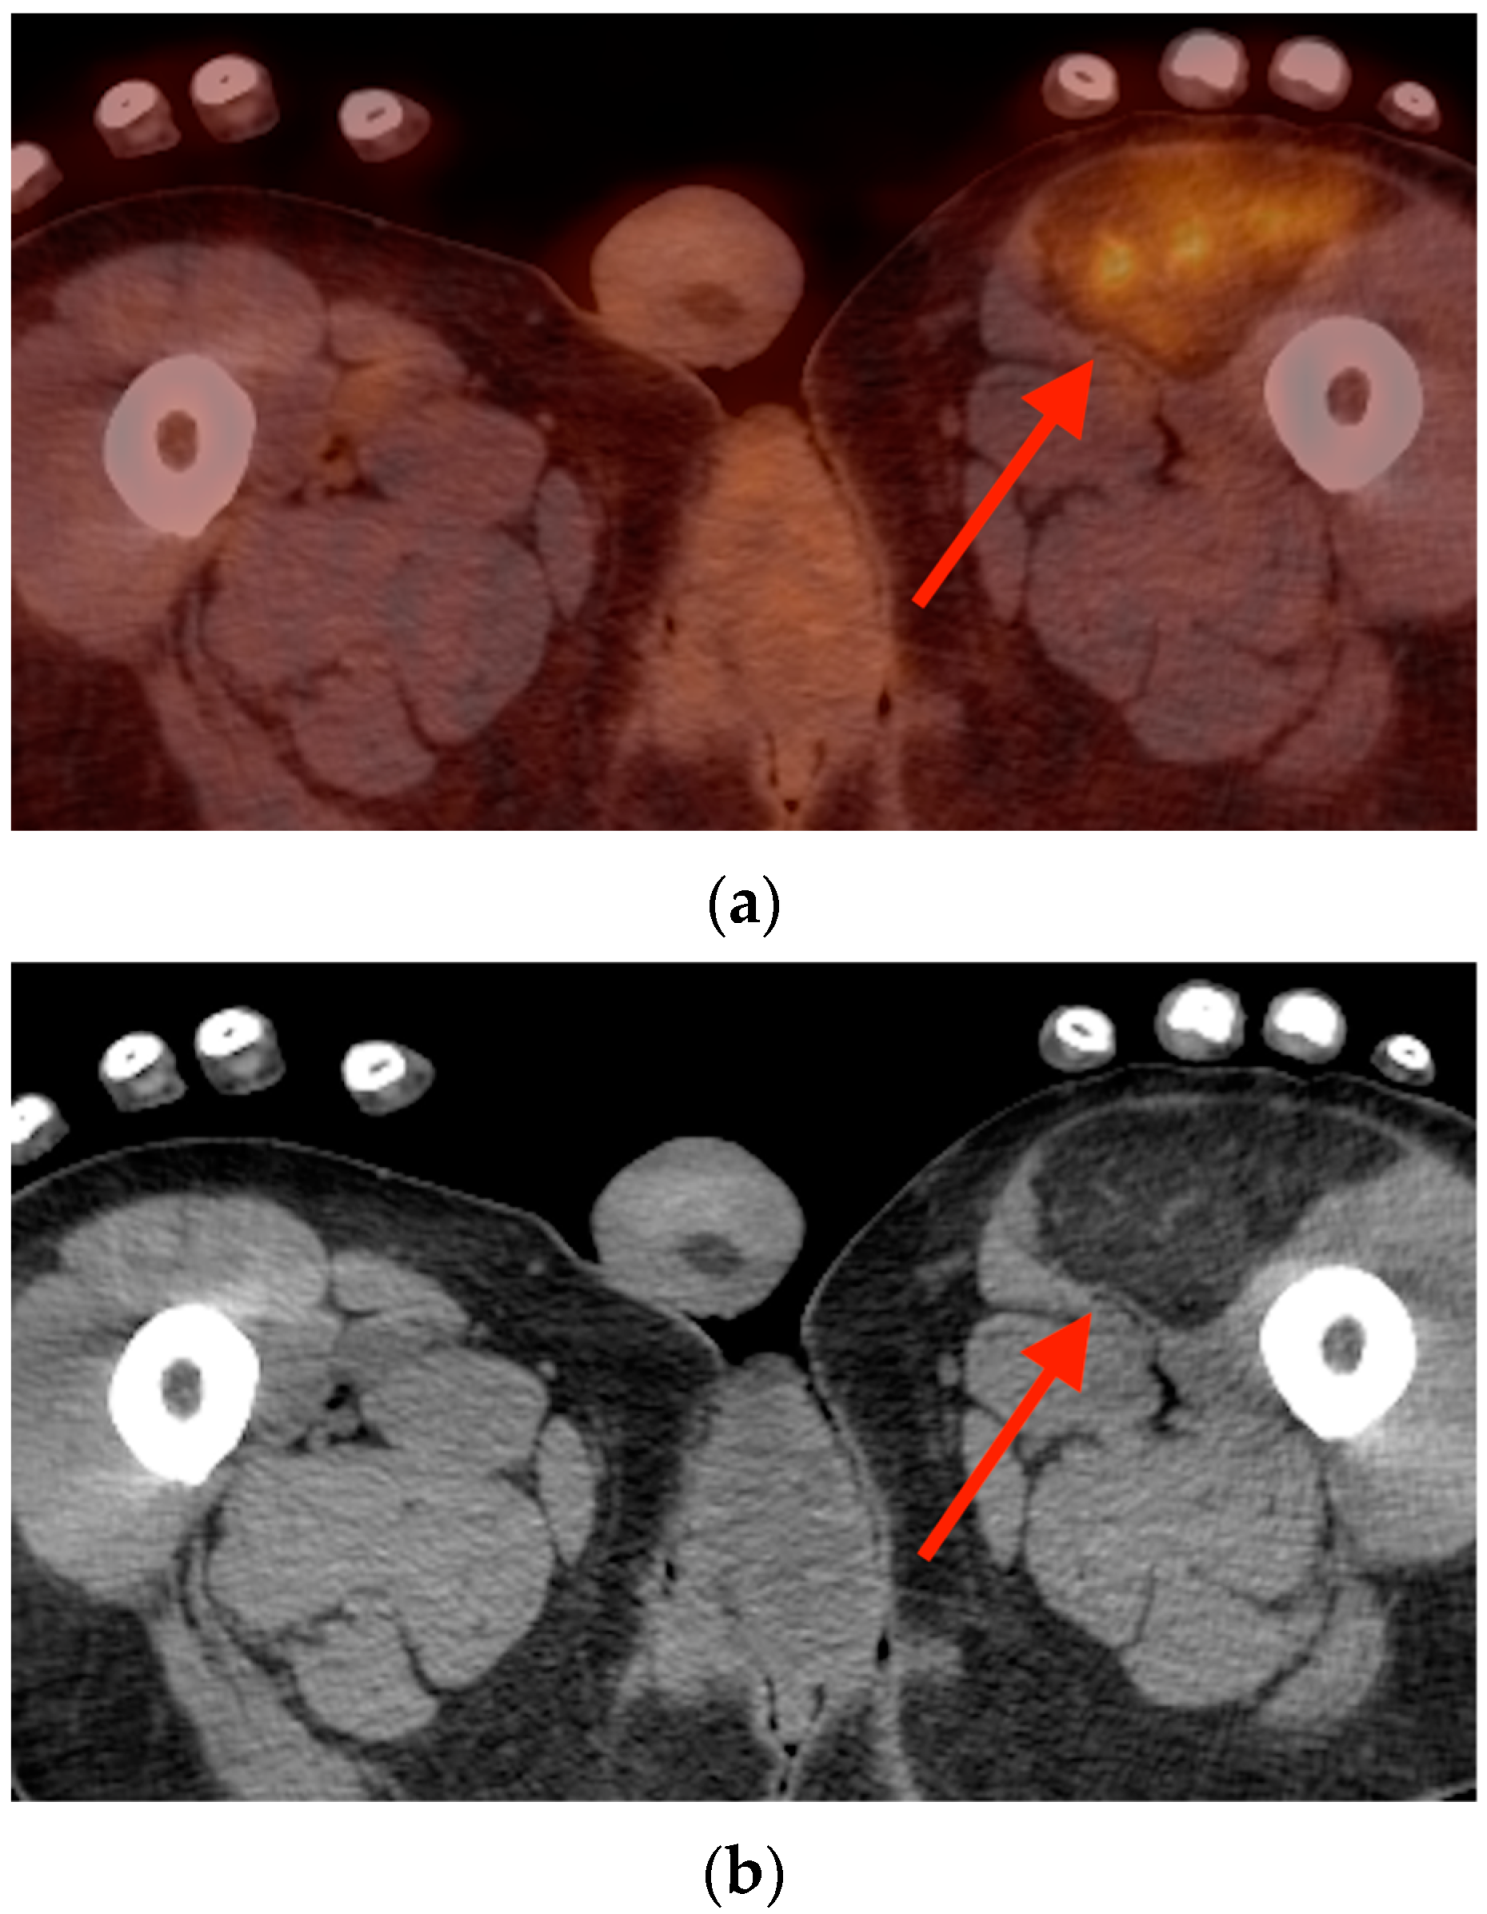

5.1. Fat Necrosis

5.2. Brown Fat Activation